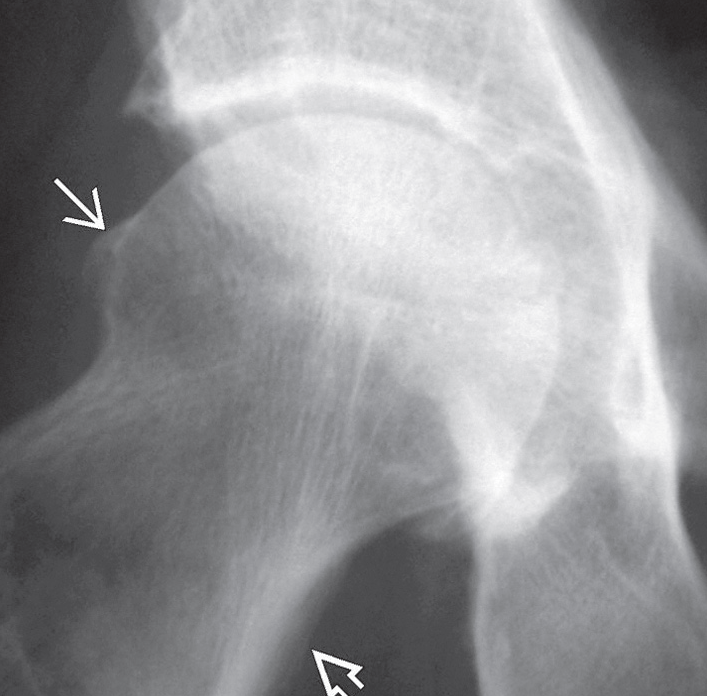

Hastanın teşhisini koymak ve hangi derecede kireçlenmesi olduğunu anlamak için birtakım tanı yöntemleri kullanılır. Hastanın şikayeti ve hikayesinden kalça ağrısının boyutu ve bunun günlük aktiviteleri etkileme derecesi hakkında bilgi sahibi olunur. Takiben fiziksel muayene ile kalça hareketliliği ve gücü değerlendirilir. Fiziki muayenenin ardından yıpranmanın kesin tanısı, boyutu ve nedenlerinin tespiti için röntgen çekilir. Bazen kalçadaki kemik ve yumuşak dokuların durumunu belirlemek için manyetik rezonans görüntüleme (MRG) taraması gibi başka testlere de ihtiyaç duyulabilir.

Kalça kireçlenmesi grafisi. Eklem aralığı daralmış.